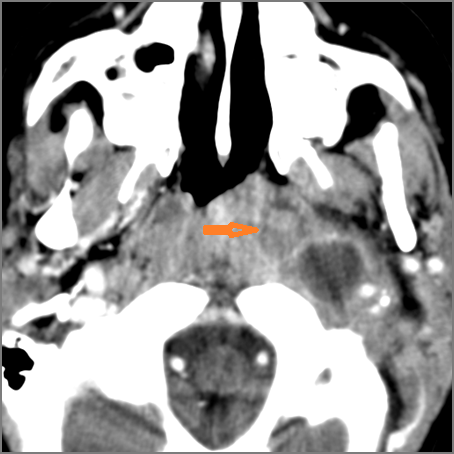

Oropharynx and Nasopharynx

There is excessive enhancement or thickening of the mucosa or hypertrophy of the pharyngeal, palatine or lingual tonsillar tissue or the lymphoid tissue along the glossotonsillar sulci and posterior pharyngeal wall. [Yes/No]

There is an abscess relatively centrally within the lymphoid tissue of the palatine tonsil. [Yes/No]

There is evidence of a developing abscess at the periphery of the lymphoid tissue of the palatine tonsil within the potential peritonsillar space. [Yes/No]

There is edema or abscess within the fat of the adjacent parapharyngeal and retropharyngeal space. [Yes/No]